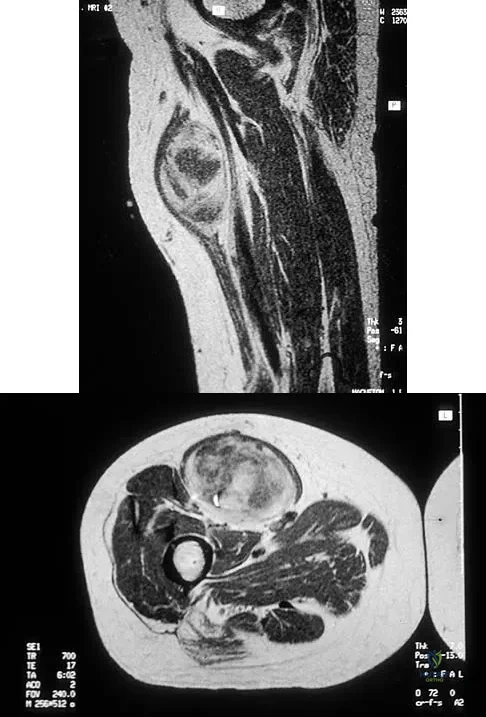

Figure 29a shows the clinical photograph of a 26-year-old woman who has had the leg deformity since birth. She reports difficulty with walking and weight bearing and notes increased discomfort and swelling when the leg is dependent. She denies any history of trauma or family history of a similar disorder. Examination reveals a fixed equinovarus deformity of the foot but no evidence of a limb-length discrepancy. No other cutaneous findings or soft-tissue masses are noted. Sagittal and axial T1- and T2-weighted MRI scans are shown in Figures 29b and 29c. What is the most likely diagnosis?

Explanation